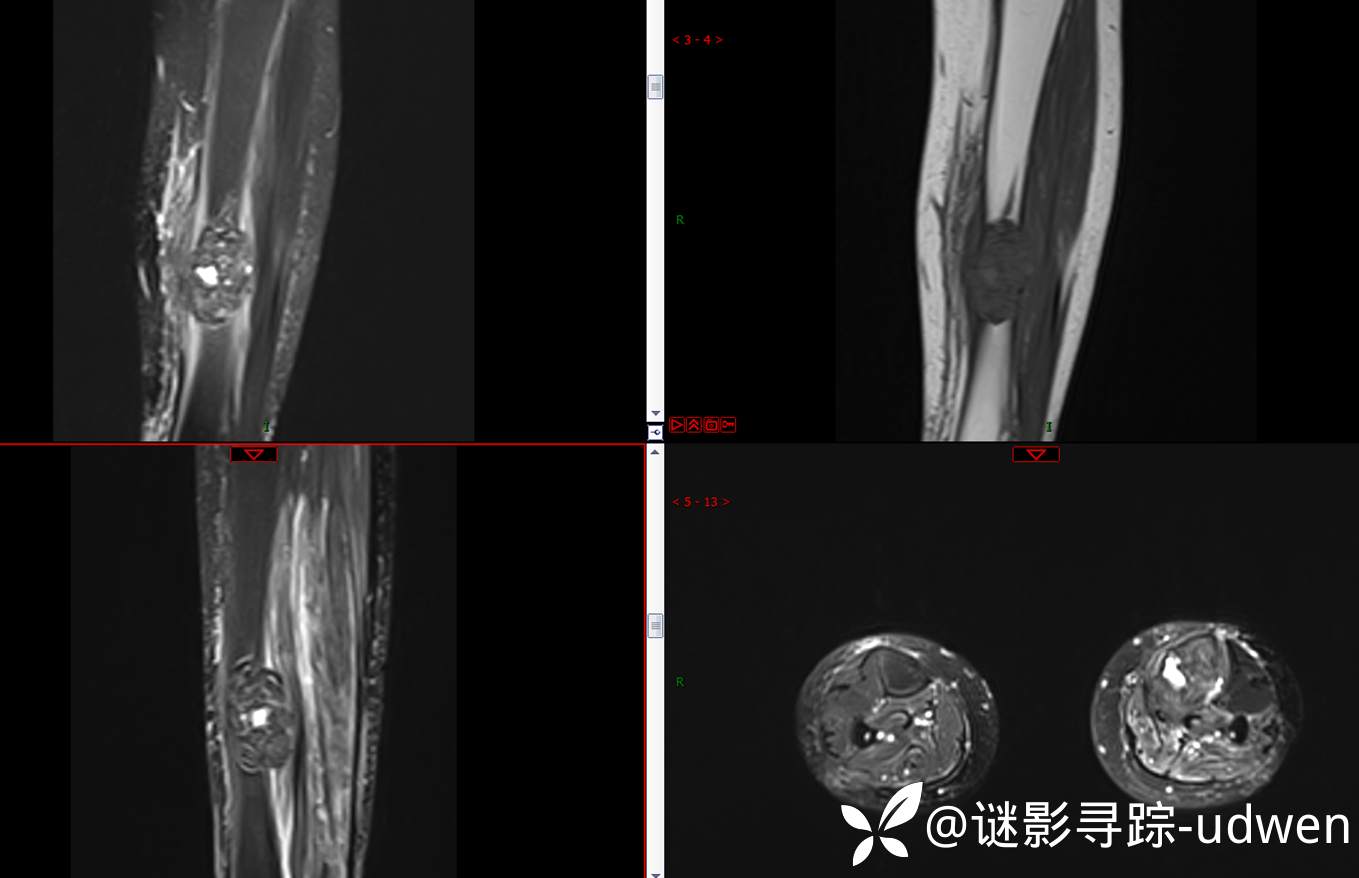

患者性别:女

患者年龄:59岁

主诉:左小腿疼痛伴活动受限半年余

简要病史:患者本人及家属诉半年余前无明显诱因出现左小腿疼痛,疼痛逐渐加重,伴活动受限,无静息痛,无发热,无头痛、头晕,无咳嗽、咳痰,无胸闷、心悸、呼吸困难,无恶心、呕吐等不适

补充MRI平扫